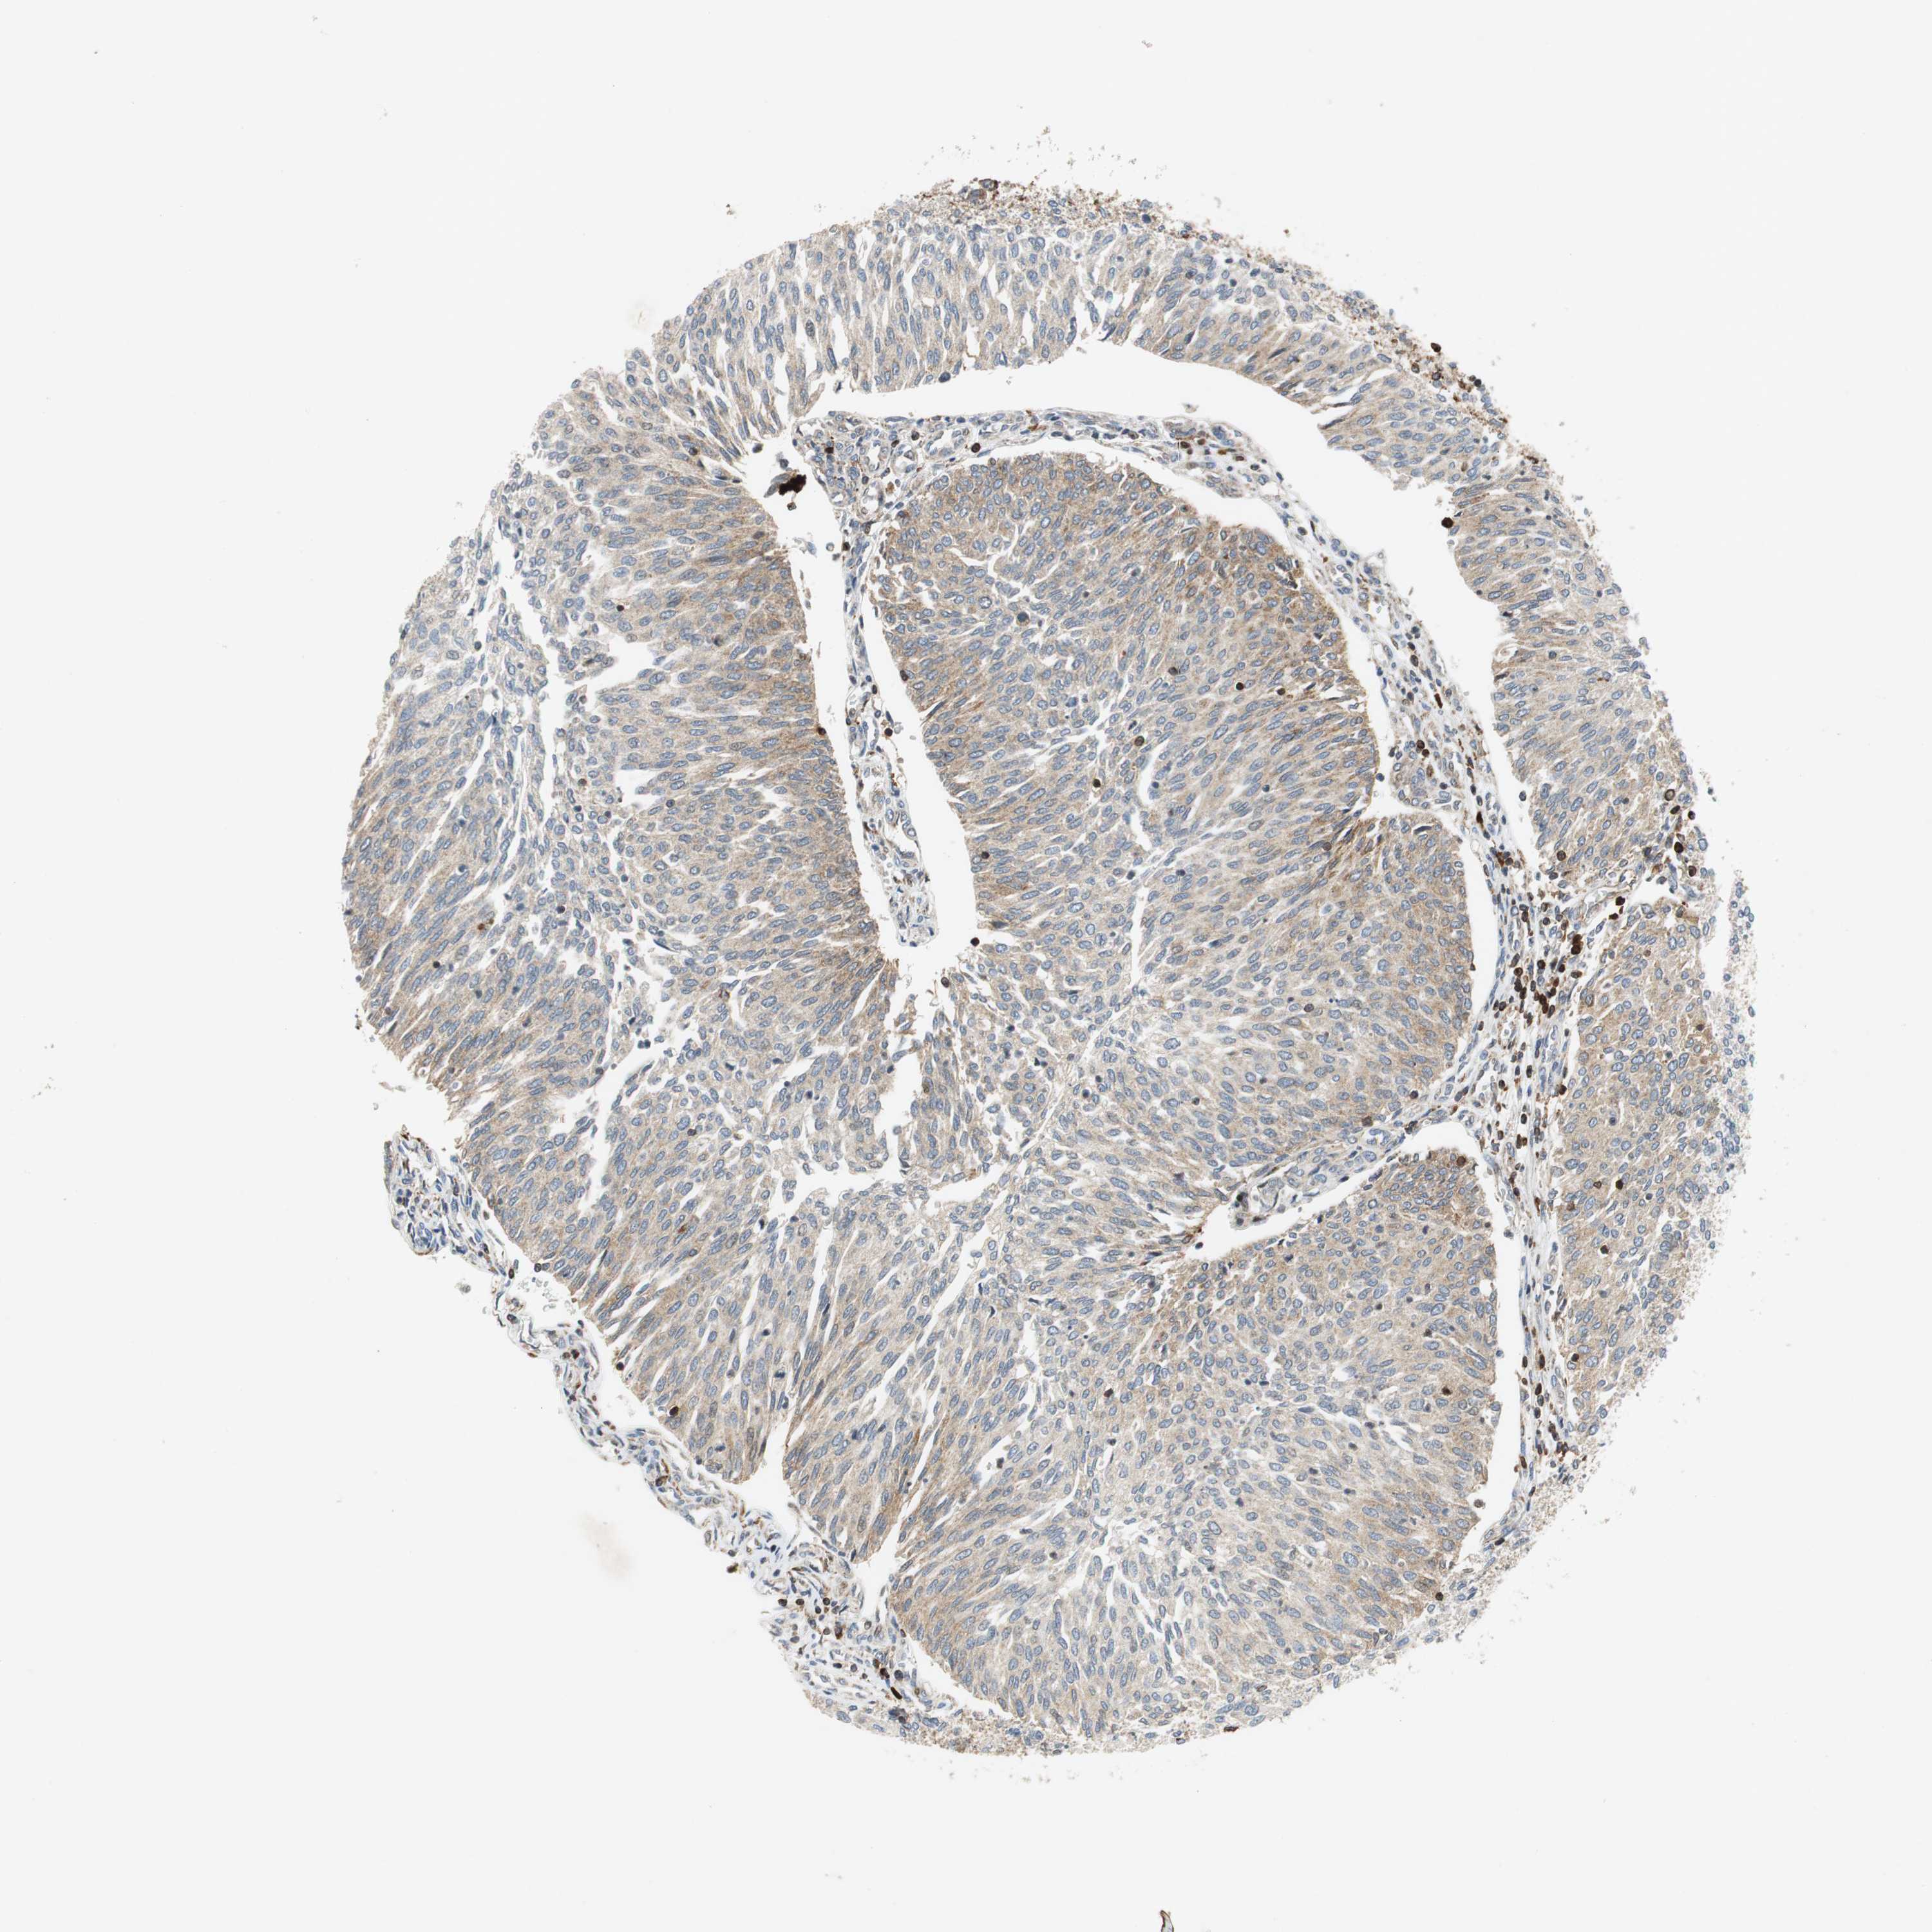

UROTHELIAL CANCER - Protein expressioni

A mouse-over function shows sample information and annotation data. Click on an image to view it in a full screen mode. Samples can be filtered based on level of antibody staining by selecting one or several of the following categories: high, medium, low and not detected. The assay and annotation is described here.

Note that samples used for immunohistochemistry by the Human Protein Atlas do not correspond to samples in the TCGA dataset.

Antibody stainingi

Antibody staining in the annotated cell types in the current human tissue is reported as not detected, low, medium, or high, based on conventional immunohistochemistry profiling in selected tissues. This score is based on the combination of the staining intensity and fraction of stained cells.

Each image is clickable and will lead to virtual microscopy that enables deeper exploration of all samples and also displays staining intensity scores, fraction scores and subcellular localization as well as patient and tissue information for each sample.

HPA039247

HPA043684

HPA063394

CAB004621

CAB005887

Staining

High

Medium

Low

Not detected

Intensity

Strong

Moderate

Weak

Negative

Quantity

>75%

75%-25%

<25%

None

Location

Nuclear

Cytoplasmic/membranous

Cytoplasmic/membranous,nuclear

Urothelial carcinoma, High grade

Urothelial carcinoma, Low grade